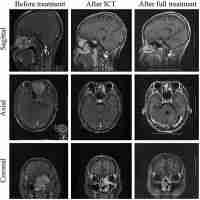

| Abstract | Background: To investigate the efficacy of induction chemotherapy followed by concurrent chemotherapy and helical tomotherapy in adult patients with locally advanced small-round-cell malignancy of the nasal cavity and paranasal sinus in regard to orbital organ preservation and quality of life. Methods: Clinical data of 49 cases of patients with orbital involvement of locally advanced small-round-cell malignancy of the nasal cavity and paranasal sinus who received multimodal treatment for orbital organ preservation between December 2009 to January 2019 were retrospectively analysed. The treatment efficacy and side effects were assessed. The study included three different pathological types. All patients were treated with induction chemotherapy followed by concurrent chemoradiotherapy. Helical tomotherapy was applied as radiotherapy. Adverse reactions to the chemotherapy were assessed according to Common Terminology Criteria for Adverse Events, Version 3. The overall survival rate, progression free survival rate and orbital preservation rate were calculated using the Kaplan-Meier method. Results: After the multimodal treatment, The 3- and 5-year OS rates of the 49 patients were 63.8% and 54.5%, respectively, and the 3- and 5-year total PFS rates were 66.8% and 63.1%, respectively. Conclusions: Multimodal treatment could preserve the orbital organs of adult patients with small-round-cell malignancy of the nasal cavity and paranasal sinus, achieve relatively ideal organ protection and survival rates and improve the quality of life, thus providing a new treatment option for these patients. |